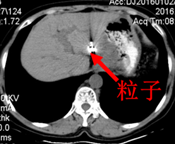

2015-10-26行CT定位下左肝占位碘125放射粒子植入术。

粒子植入术后2月CT: